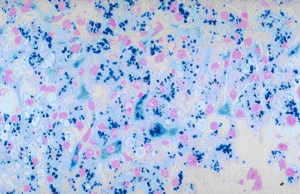

Gomori Methenamine Silver Method is designed to demonstrate urates in tissue sections. With abnormal accumulations found around joints and in soft tissues, this disturbance in uric acid metabolism is known as gout